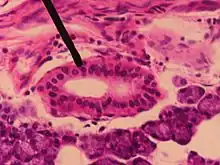

Striated duct in parotid gland

A striated duct (Pflüger's ducts) is a gland duct which connects an intercalated duct to an interlobular duct. It is characterized by the basal infoldings of its plasma membrane, characteristic of ion-pumping activity by the numerous mitochondria.[8][9] Along with the intercalated ducts, they function to modify salivary fluid by secreting HCO3 and K+ and reabsorbing Na+ and Cl using the Na-K pump and the Cl-HCO3 pump, making the saliva hypotonic.

Their epithelium can be simple cuboidal or simple columnar.[10]

Striated ducts are part of the intralobular ducts.

They are found in the submandibular gland,[11][12] sublingual duct, and the parotid gland, but are more developed in the parotid gland.[13]